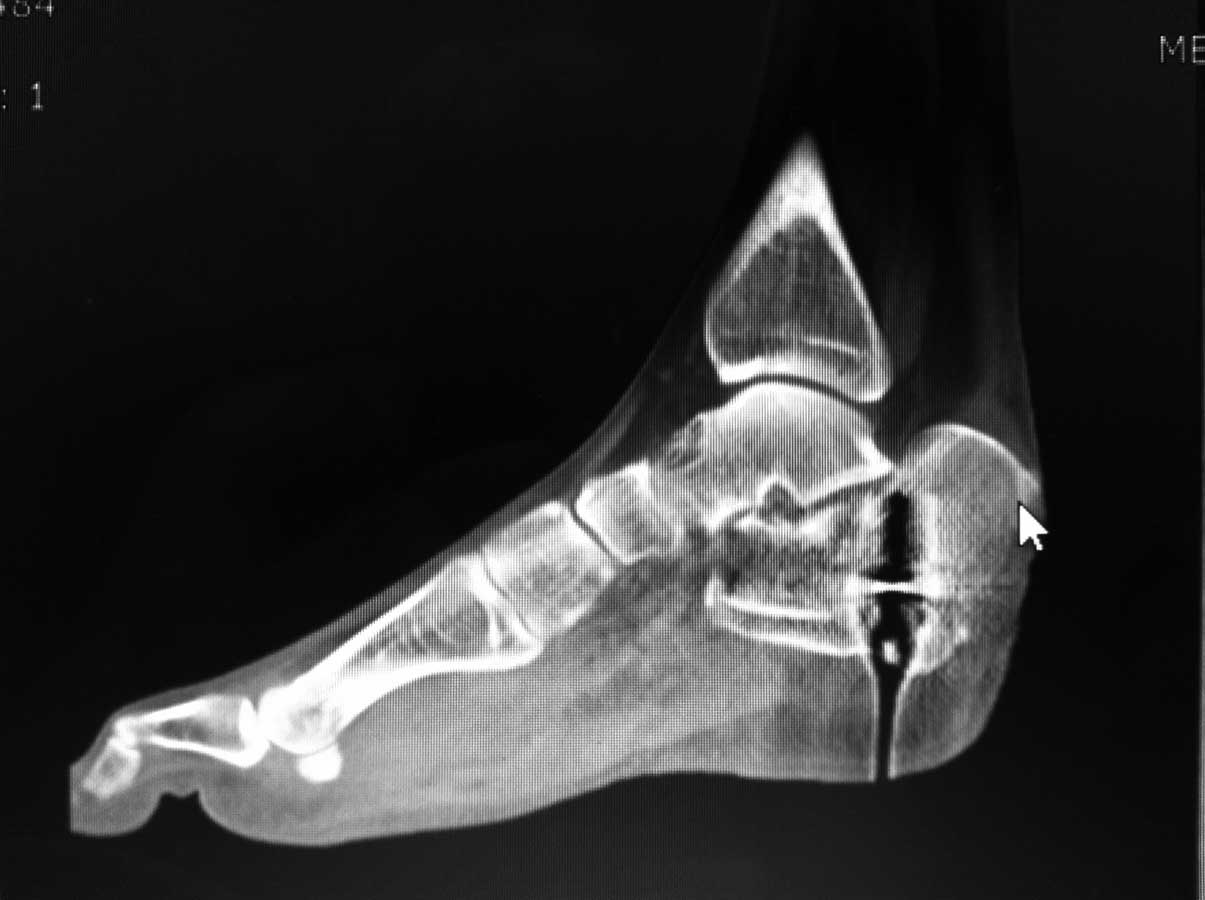

немного КТ

На аппарате к сожалению не возможно провести репазицию отломков при оскольчатых переломах пятки. Единственное что вы добетесь это востановите свод стопы. Так как поциент молодой я всётаки склонен к открытому методу используя специальную пластину. Во время операции будте внимательны к мягким тканям.

Используйте extensile латеральный L-доступ по Sangeorzan острым путем, до пяточного бугра. Используйте AO Y-пластину или реконструкционную. При ушивании идите от обоих углов к центру